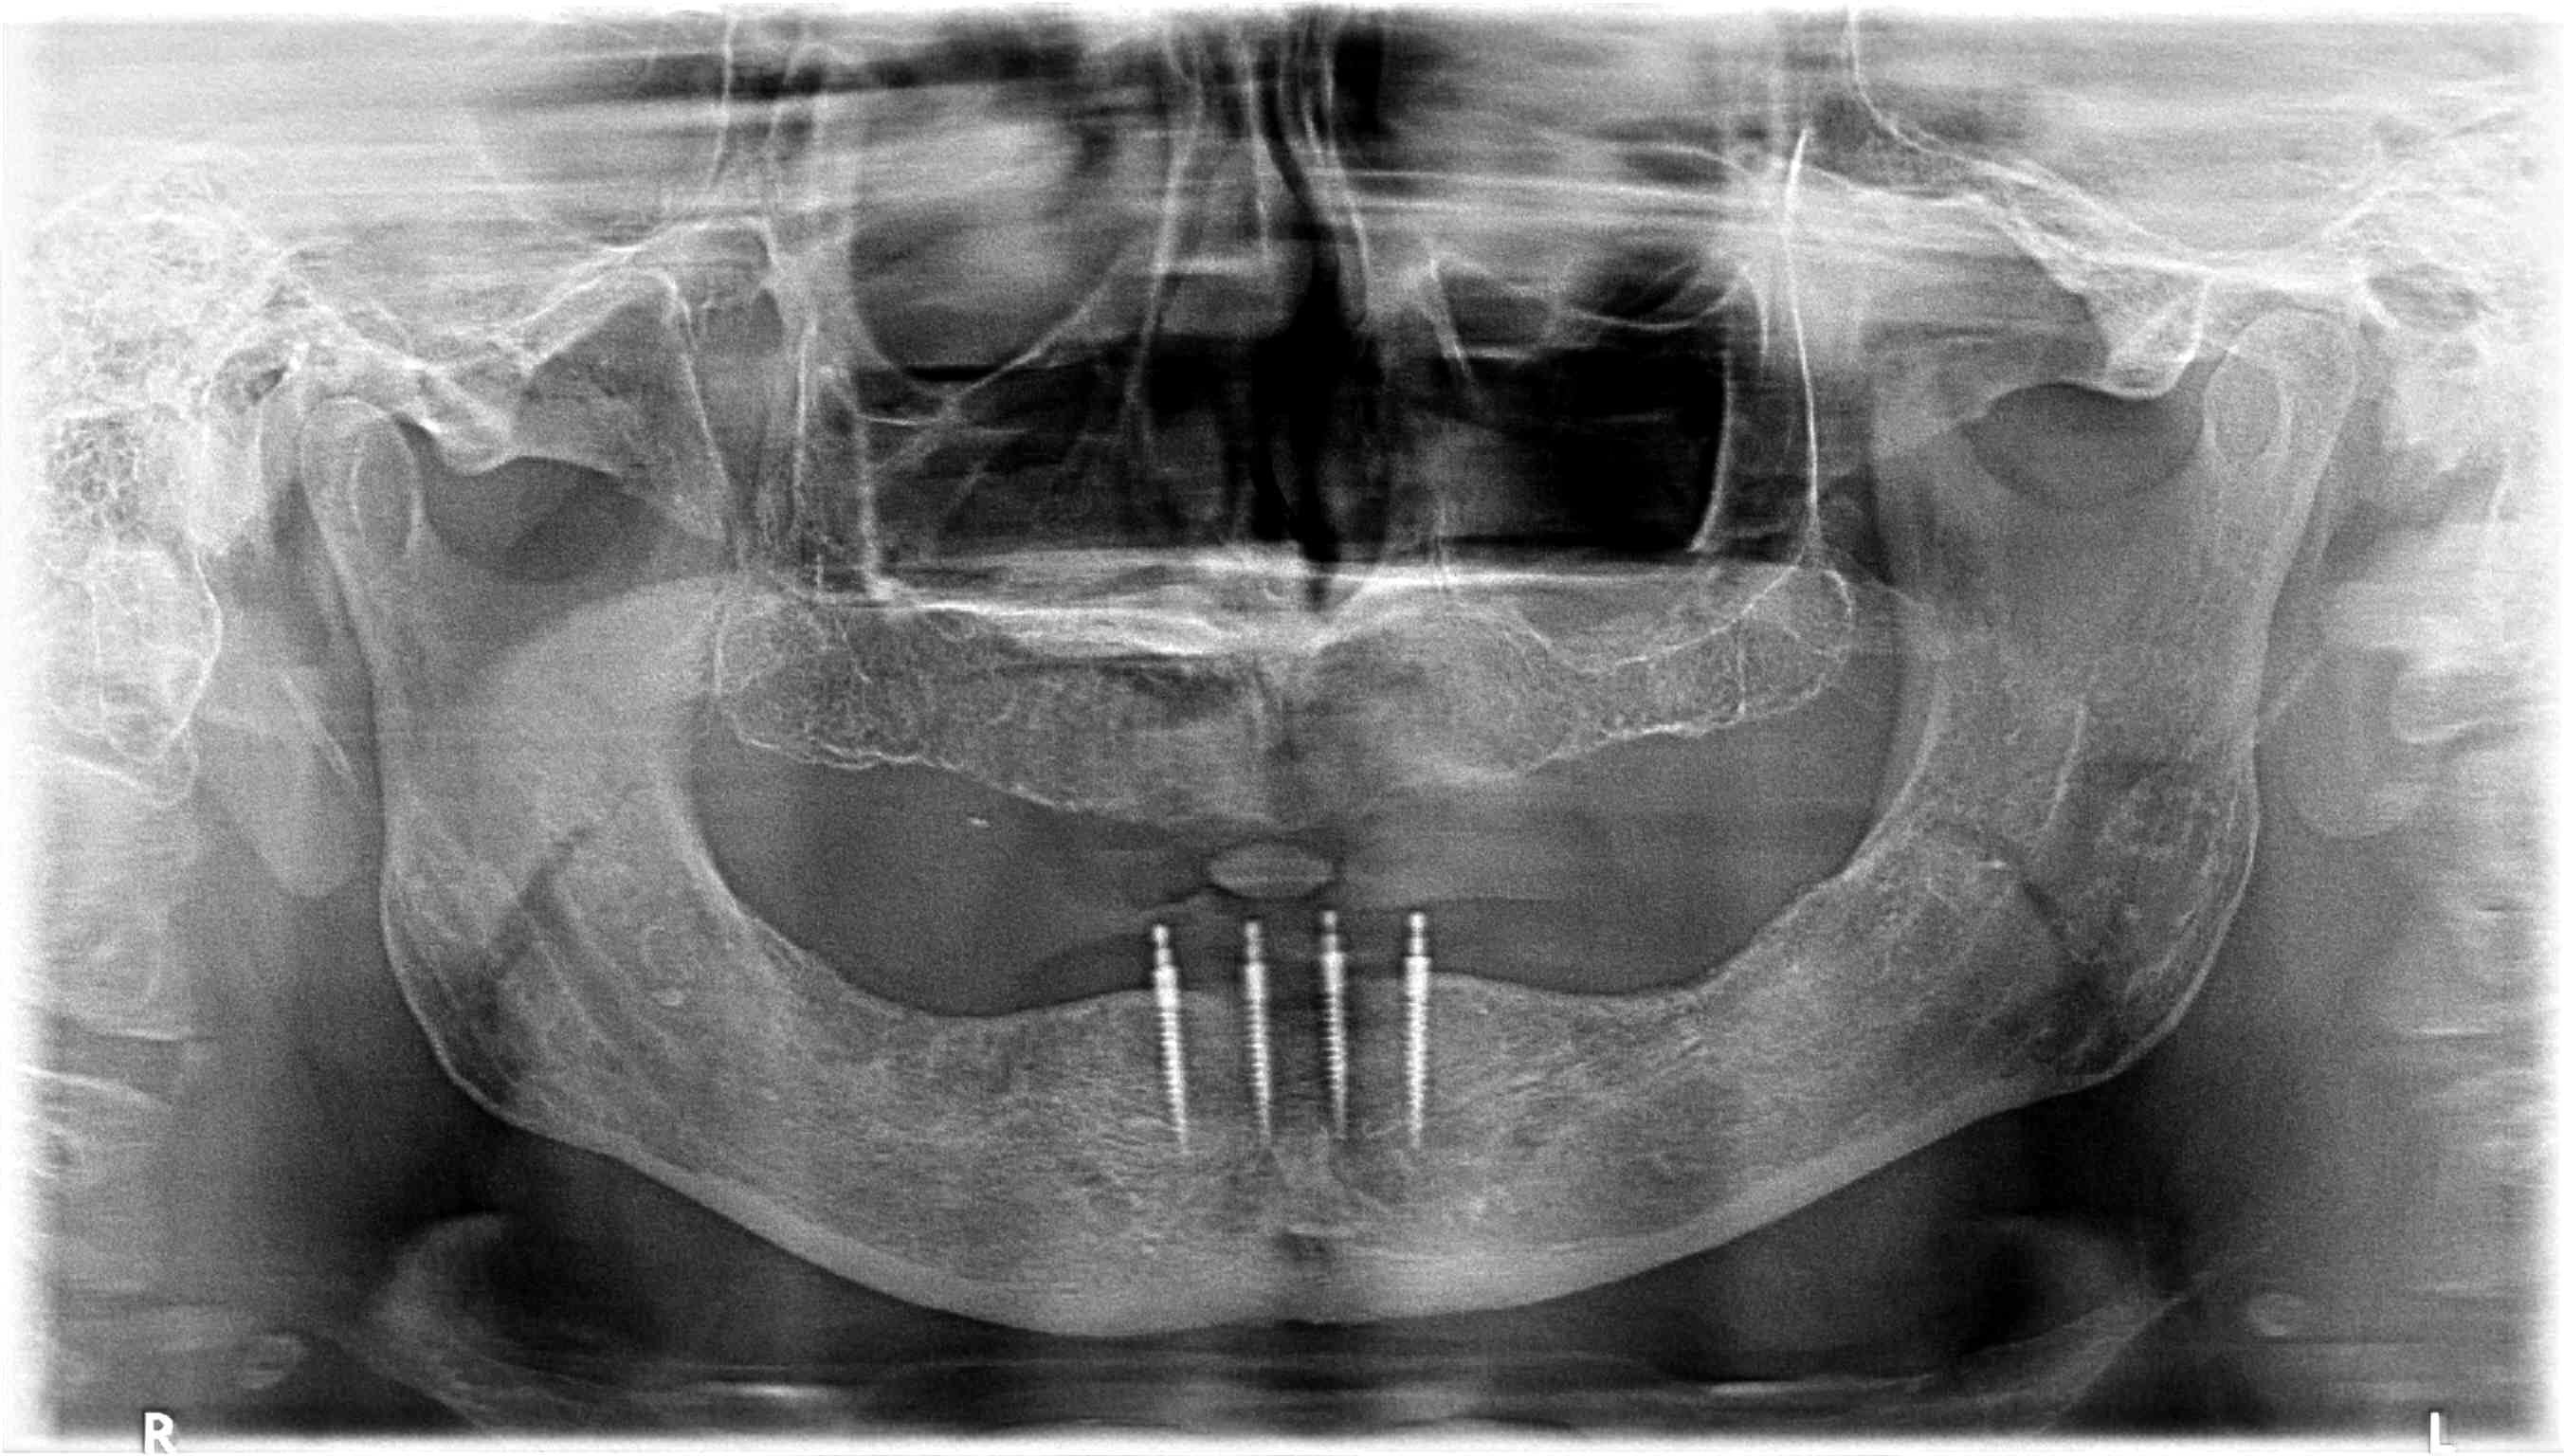

In a statement of position, the American Academy of Oral and Maxillofacial Radiology recommends that a form of cross-sectional imaging be used to guide surgical implant placement.20 In this case a small-volume cone-beam computed tomography (CBCT) scan was taken of the anterior mandible to further develop the surgical plan. From these images the position of the mental foramen and any anterior loop of the mental nerve was established (Figure 1). Given the length and width of bone, four 2.4-mm-wide by 13-mm-long implants were chosen for this case. The position of the two distal implants would allow for a margin of safety in regards to the mental nerve but would be placed as far posterior to the two most anterior implants as allowable. Maximizing the anterior-posterior, or A-P, spread of the implants would minimize any cantilevering forces acting on the denture.

Fig 1. CBCT image of the mandible with implants superimposed

Figure 1